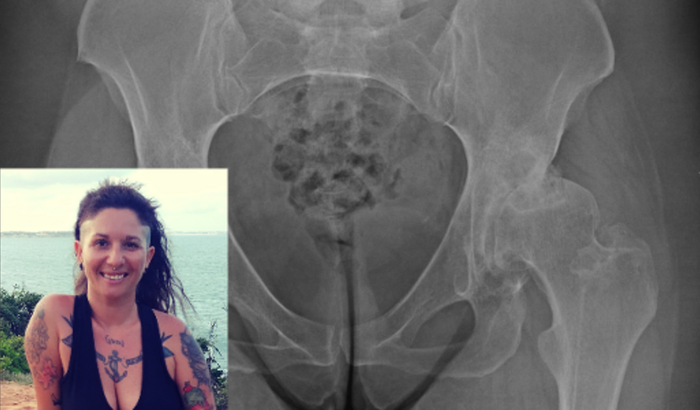

Olá, sou Veronica Pini, tenho 40 anos. Recentemente visitei um especialista de quadril devido a fortes dores que estava sentindo, porém para minha surpresa descobri que nasci com deslocamento de quadril, o qual se agravou após o acidente que sofri quando tinha 17 anos.

O referido especialista informou-me que tenho"Displasia do quadril" que está limitando cada vez mais a realização das minhas atividades diárias, por isso preciso fazer uma cirurgia URGENTE para colocar uma prótese no quadril, que tem um custo de R$34.000,00(somente a prótese)